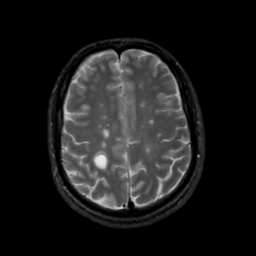

MR Study #3, February 24, 1991 -- Slice #36

[Home][Help][Clinical][Tour 1][Tour 2] Slice 36